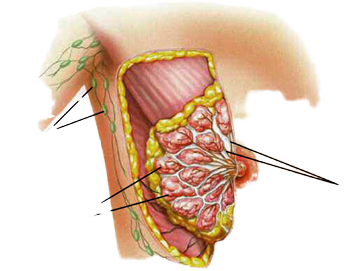

Carcinoma mammario metastatico, “curabile ma non guaribile”

Tra le novità, la pagina Facebook ospiterà fino a ottobre la “Life Academy”, lezioni online, curate da coppie di influencer ed esperte. Attraverso ricette, esercizi di yoga, illustrazioni e giochi creativi si vogliono sostenere le donne con tumore al seno. Grazie alla partnership con “My Cooking Box”, poi, “È tempo di vita” porta a casa delle donne ingredienti e istruzioni per realizzare una ricetta sana e gustosa, ideata dall’esperta enogastronica e volto televisivo Chiara Maci e dalla biologa e nutrizionista dell’Istituto Nazionale dei Tumori di Milano Anna Villarini. Sono 37mila le donne con un carcinoma mammario metastatico. L’incidenza stimata del tumore al seno in fase avanzata è di 14 mila casi all’anno, di cui 3.400 già metastatici all’esordio. “Oggi – conclude Saverio Cinieri, presidente eletto Aiom, Associazione italiana di oncologia medica- è una malattia curabile, anche se non guaribile. Le prospettive di sopravvivenza sono aumentate ed è possibile tenere sotto controllo la malattia anche per lungo tempo”.